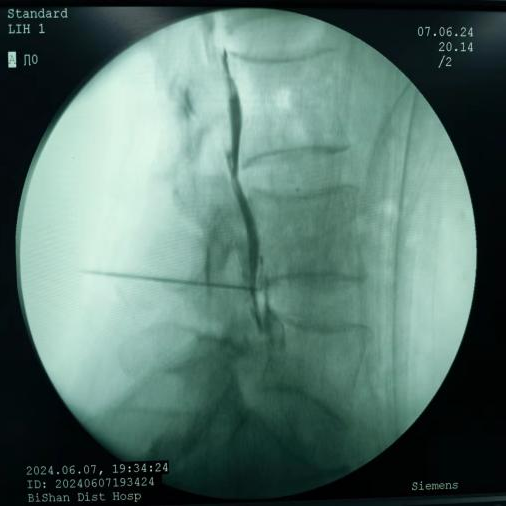

鞘內(nèi)泵植入術(shù):將藥物輸注導(dǎo)管植入鞘內(nèi),通過體外或體內(nèi)泵持續(xù)輸入鎮(zhèn)痛藥物,作用于中樞阿片受體,治療癌痛及頑固性疼痛。

圖片

鞘內(nèi)泵植入術(shù)